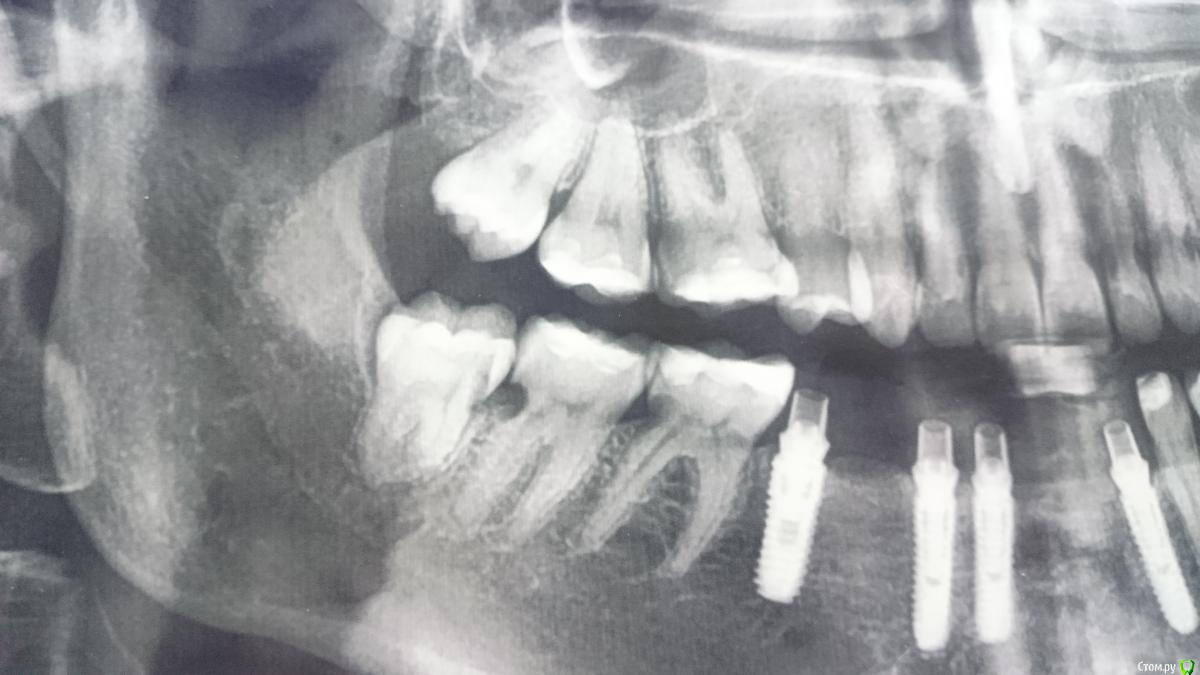

lightella Опубликовано 6 февраля, 2018 Поделиться Опубликовано 6 февраля, 2018 Здравствуйте, коллеги. В клинику обратилась пациентка 1989г.р.Орто 2015г.А это уже 2017Девушка в отчаянии, мы тоже че то приуныли.Кто может - пожалуйста, поделитесь опытом или информацией. Ссылка на комментарий

lightella Опубликовано 8 февраля, 2018 Автор Поделиться Опубликовано 8 февраля, 2018 (изменено) воздержусь до ответовОтвечаю. Девушка не спортсменка. Соматически здорова (обследовалась вдоль и поперек именно из за данной проблемы). Единственное, к чему можно придраться - один из анализов на гормоны ЩЖ оказался на десятую долю ниже нижней границы. На этом основании выставлен гипотиреоз (вот не знаю, насколько это правомерно, учитывая, что всего один показатель нарушен). Систематический прием каких либо препаратов отрицает.Гигиена приемлемая, не идеал, но выше среднего, скажем так. Множественого кариеса нет. Насколько я знаю, пациентка смирилась с тем, что лишится зубов. Знать бы еще, какие подводные камни могут быть при имплантации в подобных случаях. Изменено 8 февраля, 2018 пользователем lightella Ссылка на комментарий

lightella Опубликовано 8 февраля, 2018 Автор Поделиться Опубликовано 8 февраля, 2018 Резорбция не кариес. Тут нет такой зависимости от гигиены .Я так понимаю, доктор (dentikl) имеет в виду, что резорбцию спровоцировала агрессивная профгигиена. Не берусь утверждать, но мне это кажется маловероятным.тогда речь Может Идти о сочетании неудачной гигиены и удачной последней панорамы.Поясните, пожалуйста. Особенно насчет панорамы - в чем ее удача? И еще, по поводу связи со спортом интересно. Как у нее было изначально с гигиеной?Как это оценить ретроспективно? Как было с финансами в 15 году?Не знаю. И в каком контексте об этом спросить пациентку - тоже не знаю. По поводу чего в 15 делали панорамуВозникли жалобы, панорама была для предварительной диагностики. почему не вмешивались тогда? Вполне себе вмешивались, депульпировали и даже протезировали. В нашу клинику она попала только сейчас, даже импланты не наши.Ваш врачебный опыт и специализация?Терапия. В каких величинах измеряется опыт я не знаю. 10 лет +/- декрет. Ссылка на комментарий